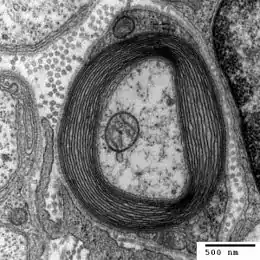

As an autoimmune disease, multiple sclerosis is caused when an individual's immune system begins attacking healthy body tissues. Specifically, immune cells begin to attack the myelin surrounding axons throughout the nervous system, thereby severely crippling the nervous system's ability to transmit signals. After neurons have their axons damaged in this way, scars (or scleroses) form, which in turn increase the rate of degeneration. The fact that this autoimmune assault may take place anywhere throughout the central nervous system (or, more commonly, in a number of locations at once), the precise symptoms that will result are difficult to predict. For example, degradation of spinal chord axons may contribute to movement difficulties, while in the brain this same degradation may result in psychological consequences. Multiple sclerosis has a fairly strong genetic component, but what exactly triggers the immune system to start attacking the body is unknown.